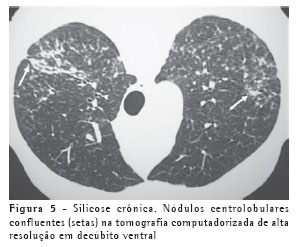

Os achados iniciais na TCAR consistem em micronódulos centrolobulares e subpleurais (Figura 4), menores que 0,5 cm. Com a evolução da doença estes micronódulos tendem à confluência, com formação de nódulos maiores (Figura 5), conglomerados (Figura 6) e, numa fase mais tardia, massas fibróticas, geralmente com calcificações e aumento irregular do espaço aéreo adjacente (Figura 7).(5)